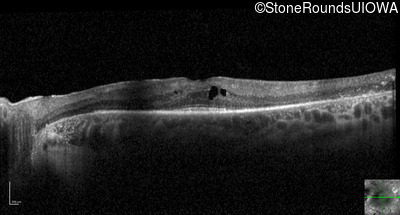

Optical Coherence Tomography - Left - 20/32

Exemplar / OCT Stack

OCT Stack